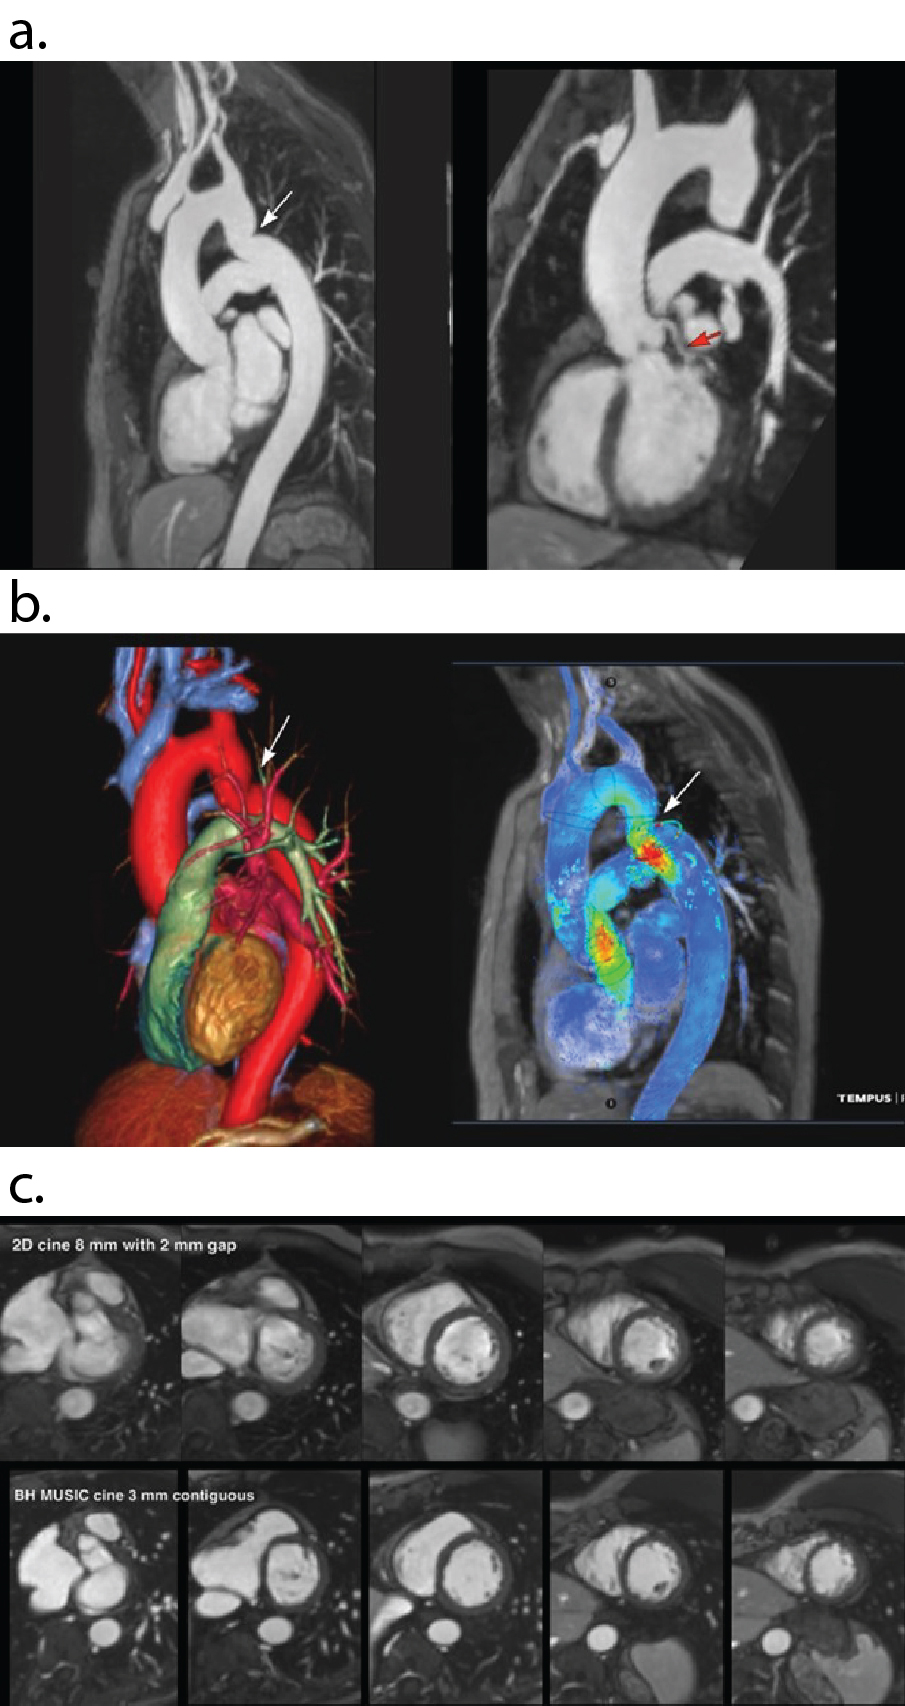

Figure 2: 42 y.o. female with mild aortic coarctation. a) Multiplanar reconstructions on OsiriX software displays one of 10 phases from BH 4D MUSIC at 3.0T . Breath-hold duration 22 secs with acceleration factor X15. Note the uniform blood signal and clear definition of the coarctation (white arrow) and left coronary artery (red arrow). b) Same patient and same acquisition as in Fig 4a. Color volume rendered frame from BH 4D MUSIC (left panel; Vitrea workstation) and corresponding 4D flow (right panel; Tempus cloud) on one of 10 phases shows the anatomy and flow field of the coarctation (arrow). c) Same patient as in Figs 2a,b. Separate BH 4D MUSIC acquisition with higher temporal resolution for full coverage cine imaging. Breath-hold duration 19 secs with acceleration factor X15. Top panel shows single phase from 2D cine at several short axis positions. Bottom panel shows corresponding short axis cine 18 phase reconstructions from BH 4D MUSIC with 3mm contiguous slices and 50 ms temporal resolution.